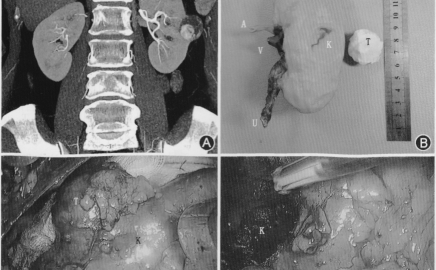

中国首例人子宫移植成功手术:母亲子宫移給女儿